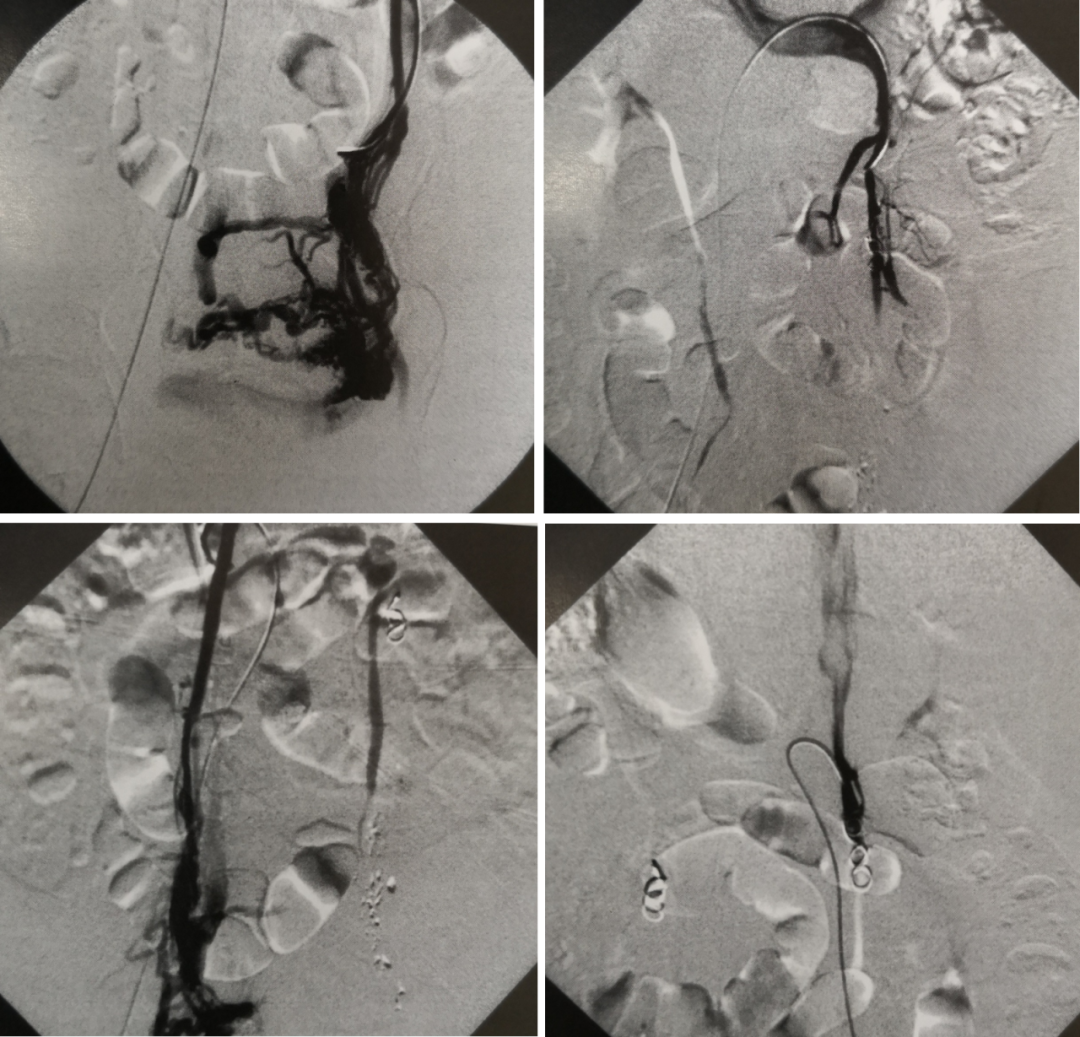

有创金标准:静脉导管造影

地位:诊断PCS的“金标准”,但属于有创操作。

适用情况:通常不用于初步诊断,而是在诊断不明确或已决定同期行介入栓塞治疗时进行。可最直观地显示反流路径、范围及侧支循环。

图:双侧卵巢静脉造影